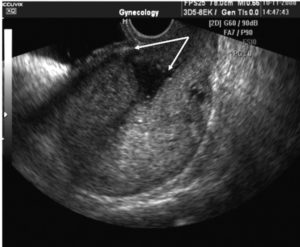

УЗИ шва матки проводится обычно трансабдоминальным методом. Это означает, что врач помещает датчик на нижнюю треть живота после планового кесарева или вблизи от средней линии при экстренно проведенной операции. Врач оценивает и фиксирует такие признаки:

- положение шва;

- ровный или есть деформации;

- наличие симптома «ниши», то есть углубления, заполненного жидкостью, участков втяжения;

- толщина стенки матки в области шва;

- соотношение мышечной и рубцовой ткани;

- движение крови около шва.